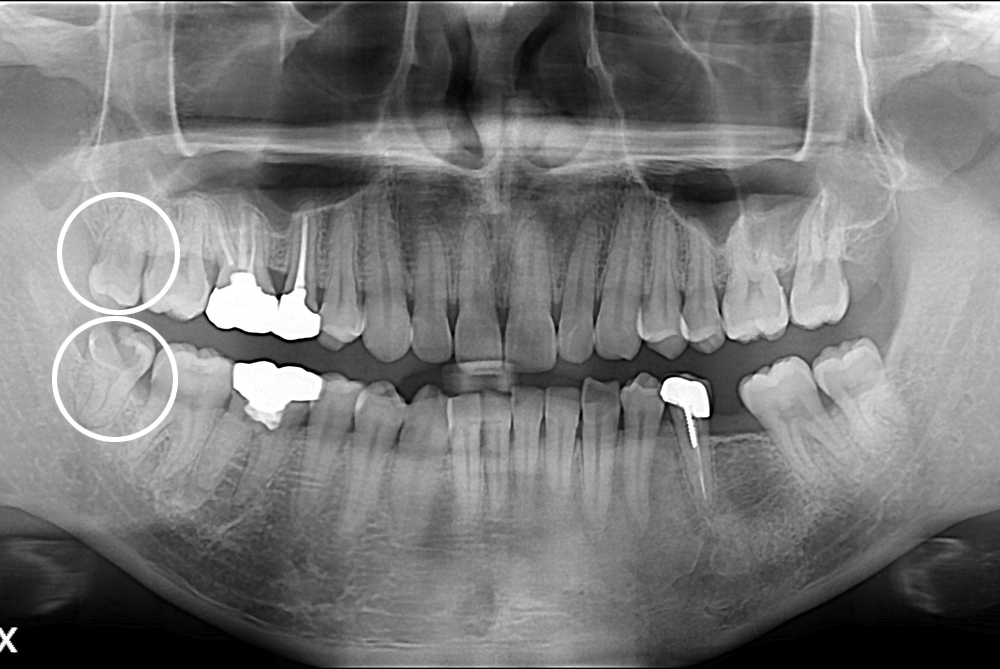

[사랑니] 난발치 사랑니 발치

치료후 : 2017-10-11